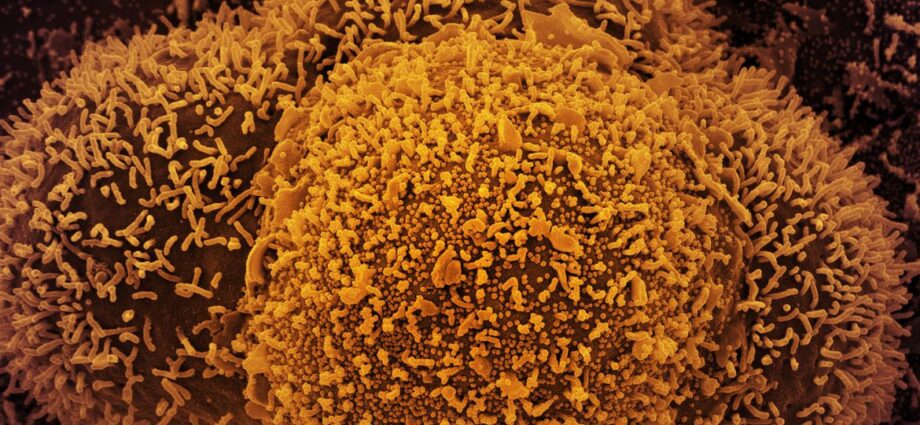

A variante XE é uma combinação de duas cepas da Ômicron: BA.1 e BA.2 | Foto: © NIAID

A variante XE é uma combinação de duas cepas diferentes da Ômicron: BA.1 e BA.2. O primeiro caso foi mapeado na cidade de Londres, em janeiro deste ano. Segundo o Instituto Butantan, a taxa de crescimento da XE é 10% superior à da cepa BA.2.